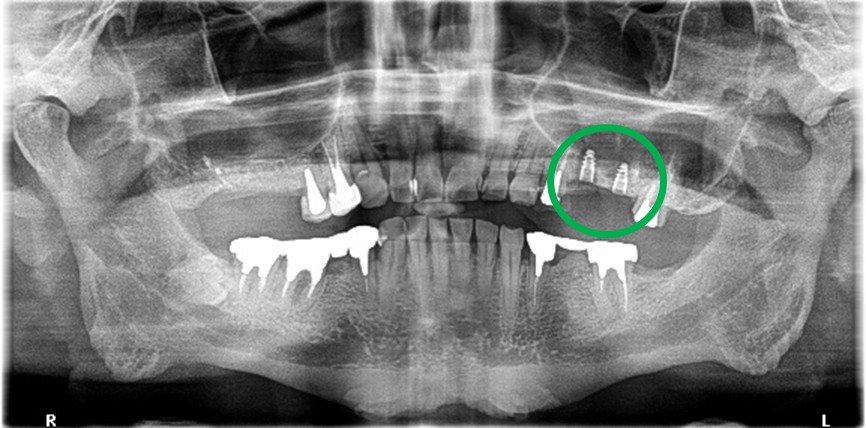

レントゲンで詳しく診てみると、虫歯が歯根のほうまで進行し、保存することができないことがわかり、抜歯しました。抜歯後、骨が大きく欠損していましたので、骨造成を行いインプラントを2本埋入しました。

所感

抜歯後の欠損したところを補う方法には、部分入れ歯、ブリッジ、インプラントがあることを説明したところ、自分の歯と同じような感覚で嚙むことができるインプラントを選択されました。この方は、2016年に右下にインプラント治療をし、インプラントの良さを十分に理解しておられましたので、今回も2本歯を失ったところにインプラント治療を希望されました。今回もX-Guideを使った埋入で、安心安全に行うことできました。

Before

【抜歯後】

After